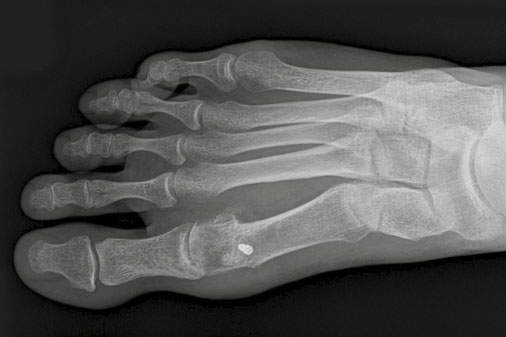

Patientin mit ausgeprägter Ballenzehe vor und 40 Tage nach Operation

Hallux valgus nach Chevron-Operation im Röntgenbild

Hallux valgus nach Scarf-Operation im Röntgenbild